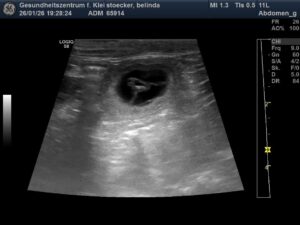

Das Date mit „Zorro vom Neunten Weinberg“ trägt Früchte.

Wie viele Welpen wir erwarten können, werden wir demnächst beim Röntgen erfahren.

Errechneter Geburtstermin ist rund um den 27.02.2026.